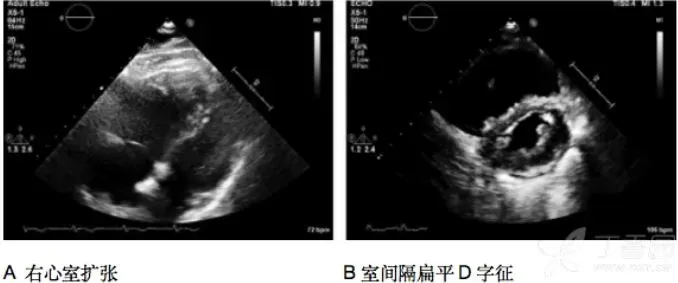

重症医学科团队迅速响应,启动重症超声评估流程。肺超示双肺对称B线、右肺下叶支气管充气征,排除气胸,与胸CT结果相符;心超见右房、右室增大,D字征,肺动脉高压伴少量心包积液;双下肢静脉超声无异常;心肌酶谱阴性。

综合各项检查结果,重症医学科团队剥茧抽丝,最终锁定病因——急性肺栓塞(中高危)合并急性心力衰竭。医护人员立即为患者实施无创呼吸辅助呼吸,同时给予充分抗凝、积极进行心衰等一系列针对性治疗措施。经过8天的精心治疗与护理,患者病情逐渐好转,顺利出院。